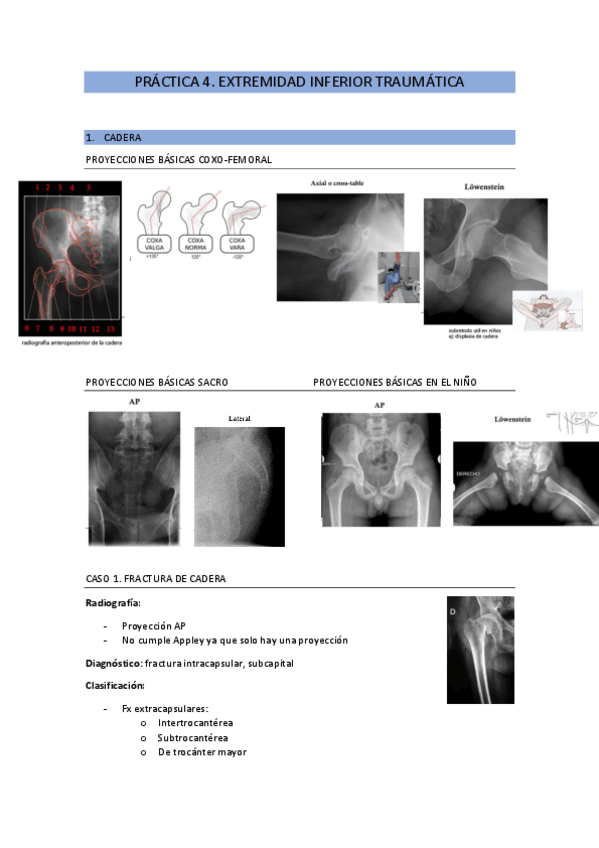

He publicado nuevos apuntes de 2º Patología y Enfoque Terapéutico del Aparato Locomotor: practica-4.-extremidad-inferiror-traumatica-pal.pdf